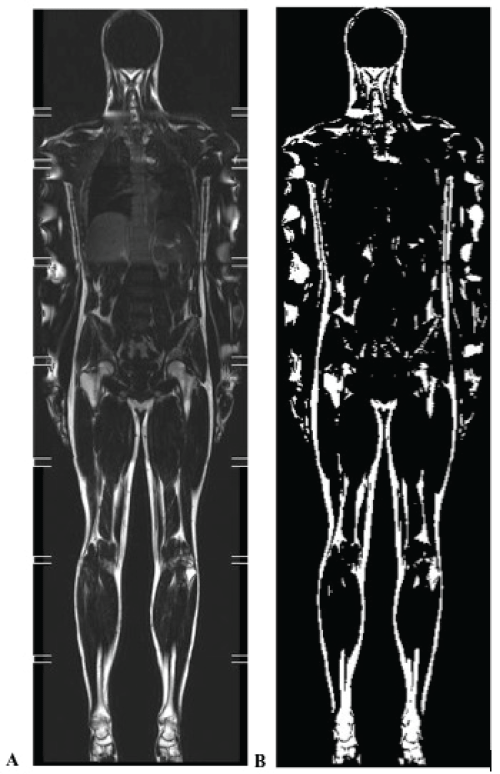

This study was cross sectional in nature. Body height was measured to the nearest 0.2cm using a stadiometer (Seca Mod 220, Hamburg, Germany). Body weight (measured to the nearest 0.05kg) and fat mass were estimated using the Multi-Frequency Body Composition Analyser MC-180MA. Fat mass was also estimated using whole body MRI (3T Philis Achieva MRI Scanner, Philips Amsterdam, and The Netherlands). Participants were scanned in the supine position using an eight station whole body imaging protocol to achieve full body coverage. The sequence used was a T1-weighted, TFE sequence with water suppression (echo time=2.3 ms, repetition time=774 MS, WFS=1 pixel, flip angle 70 degrees, spectral presaturation inversion recovery (SPIR) water suppression, NSA=2, integrated body coil). This weighting ensures that body fat is shown as hyperintense in relation to other structures in the image. The resolution of multi-slice 2D images in the coronal place was 1.83mm by 2.48mm with a slice gap of 1mm. Coronal images were reconstructed on a 1.345mm by 1 .345mm interpolated matrix. Multiple breath- holding was used to reduce motion artefact while scanning the station over the lungs and upper abdomen. Each scan generated 30 whole body coronal images. Each coronal image consisted of eight images from each of the scanned stations fused together to form a single image. Fusing was achieved using the MRI's own image fusing software (MobiView™). Images were exported to a bespoke application written in MATLAB (Mathworks, Cambridge, UK) for fat quantification. Images were thresholded using a technique called Otsu's method [22]. At each station level image in a coronal slice, a threshold pixel grey level value was chosen above which a pixel is considered to represent a fat voxel. In Otsu's method the threshold is automatically chosen by minimising the grey level variance within the above and below threshold pixel populations. The resulting operator view is a stack of 30 coronal whole body 'binary' images with 'fat' showing white and all else black (Figure 1). These binary images could be further manually edited by the operator to cut out remaining bright pixels associated with bone marrow. The total fat volume with a region of interest was calculated by a simple count of the total number of voxels above threshold in that region.

Figure 1: An example image showing an original whole body coronal image (A) and the corresponding thresholded 'fat' image (B). Note artefact on arms in A, causing water based tissues to be incorrectly included in B. Also note inclusion of bone marrow in B. Image B is further manually edited to limited analysis to a region of interest and to exclude marrow prior to fat quantification.